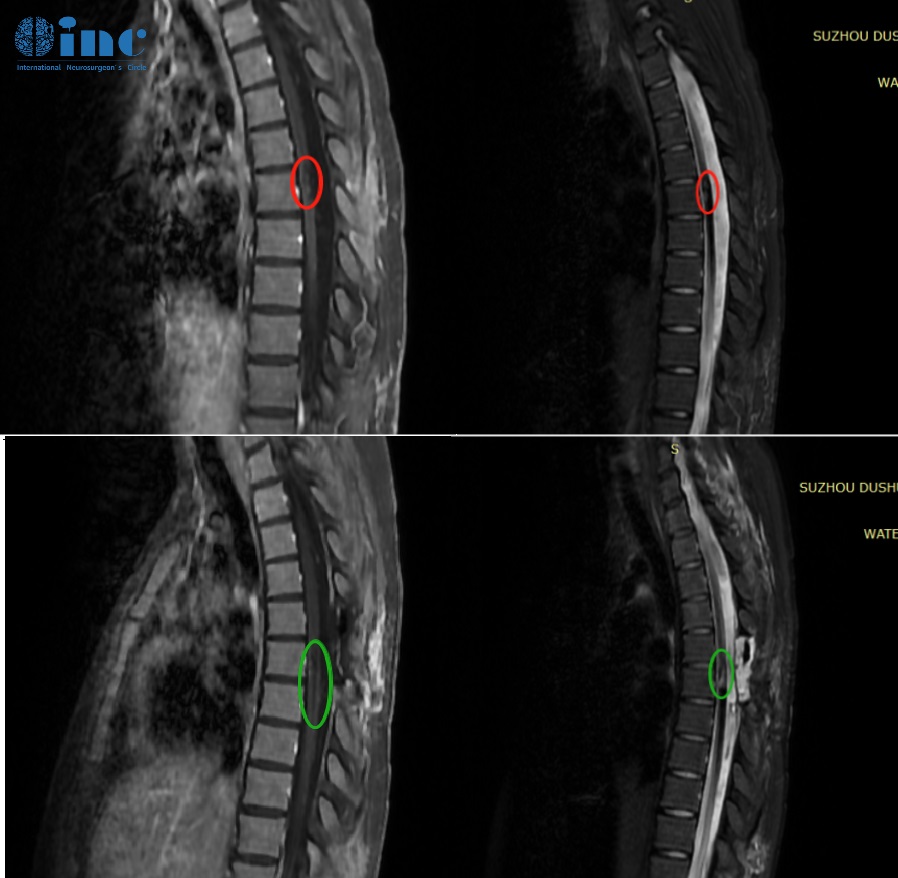

两年前,刚上大学的田田在一次参加完常规体育运动后自感后背轻微疼痛,本来以为是运动后导致的肌肉疼痛,休息几天便能够恢复。然而两天后情况并没有好转,田田甚至出现了双腿下肢无力,预感不对劲的田田赶紧就医检查,结果让年轻的她难以接受,核磁检查诊断为胸髓髓内出血性病变,怀疑海绵状血管瘤。并且后续病情进展很快,田田还出现小便困难,双下肢无力加重等症状。再次检查后确诊胸髓髓内6段海绵状血管瘤,医生考虑血管瘤位置比较深,在腹侧,手术风险大,术中稍有不慎,就可能导致术后长期瘫痪,建议保守治疗。保守治疗后田田的双腿无力症状得到缓解,可以自行行走。

而好转并没有维持多久,二次出血很快就再次来临,去年田田再次出现右下肢麻木感,检查考虑二次出血。两天内症状急剧加重,双下肢运动功能丧失,大小便失禁。为了缓解田田的症状,医院随即进行下胸后路椎管扩大减压术,但是并未对血管瘤进行切除。看到女儿一次又一次病情加重而又无能为力,田田父母开始为女儿寻求更好的治疗……

经过INC工作人员的整理翻译后,巴教授了解到田田的病例情况,对于田田目前的状况,巴教授表示“上次的出血已经在脊髓内造成严重的损害,并像“管子”中的液体一样,在脊髓内从出血的位置纵向的向上方和下方延伸”,教授可以为田田提供手术,手术虽然会在临床上程度好转田田术前已有的症状,然而需要强调的是,并非全部的症状都会消失,病人应清楚地明白这点 - 手术的主要目标就是切除残留的血管畸形,以免将来的再次出血!导致更加难以接受的症状。而自己可以为田田提供顺利摘除胸髓髓内的海绵状血管瘤手术。

这次手术的目的是把现在存在的血管瘤拿掉,因为这个海绵状血管瘤还会再次出血,造成症状会更严重,整个肢体活动可能完全就没有了。我们现在是把这个血管瘤拿掉了之后,通过康复运动,使肌力再次增加,缓解现在的症状。主要目的还是把血管瘤拿掉,防止再出血造成更大的损害。而且从影像上看,脊髓损伤的还不是很严重,孩子还年轻,症状能够减轻机会还是大的。手术之后就可以开始轻缓的康复练习,两三周之后就可以开始康复运动……